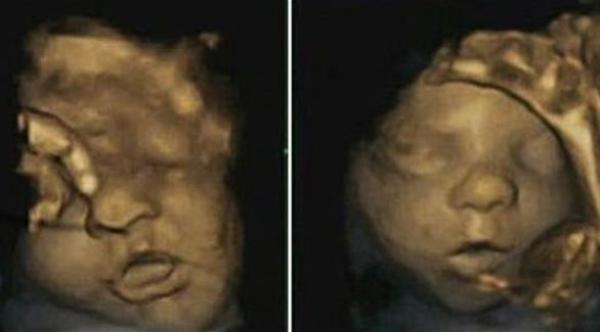

بالصور: الجنين يتمرن على الابتسام استعداداً للقاء والديه